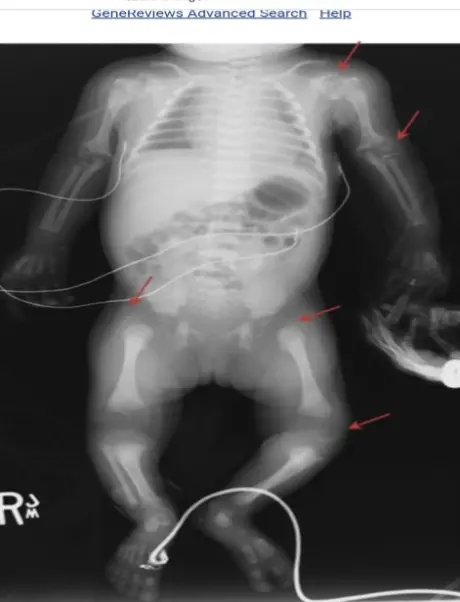

- Radiographic: Stippling of epiphyses (Chondrodysplasia punctata).

- Neurologic: Hydrocephalus, macrocephaly.

- Hematologic: Anemia, neutropenia, thrombocytopenia, rare aplastic anemia.

3. Other Manifestations

- Hepatic: Asymptomatic elevated enzymes, mild hepatosplenomegaly, cholestasis, hepatitis.